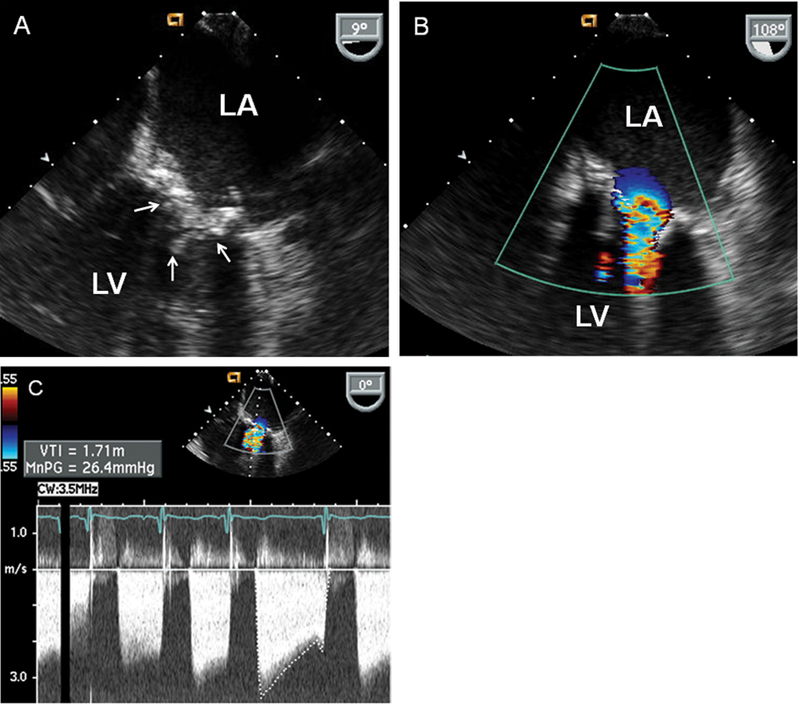

فحوصات تشخيصية لبعض امراض القلب والشرايين التاجية